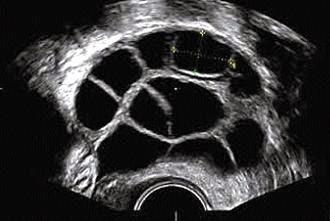

La reserva ovárica de una mujer puede estimarse mediante el análisis en sangre de ciertas hormonas. Un valor elevado de la hormona FSH (más de 10-12mUI/ml) entre el tercer y quinto día del ciclo menstrual indica una reserva ovárica reducida.

La hormona Antimulleriana también es indicadora de reserva ovárica y puede ser analizada en cualquier momento del ciclo, punto beneficioso en los estudios de fertilidad frente a la FSH.